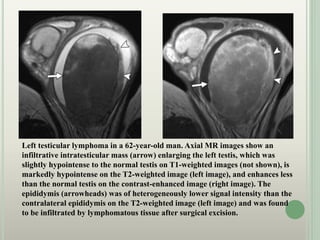

Left testicular lymphoma in a 62-year-old man. Axial MR images show an

infiltrative intratesticular mass (arrow) enlarging the left testis, which was

slightly hypointense to the normal testis on T1-weighted images (not shown), is

markedly hypointense on the T2-weighted image (left image), and enhances less

than the normal testis on the contrast-enhanced image (right image). The

epididymis (arrowheads) was of heterogeneously lower signal intensity than the

contralateral epididymis on the T2-weighted image (left image) and was found

to be infiltrated by lymphomatous tissue after surgical excision.